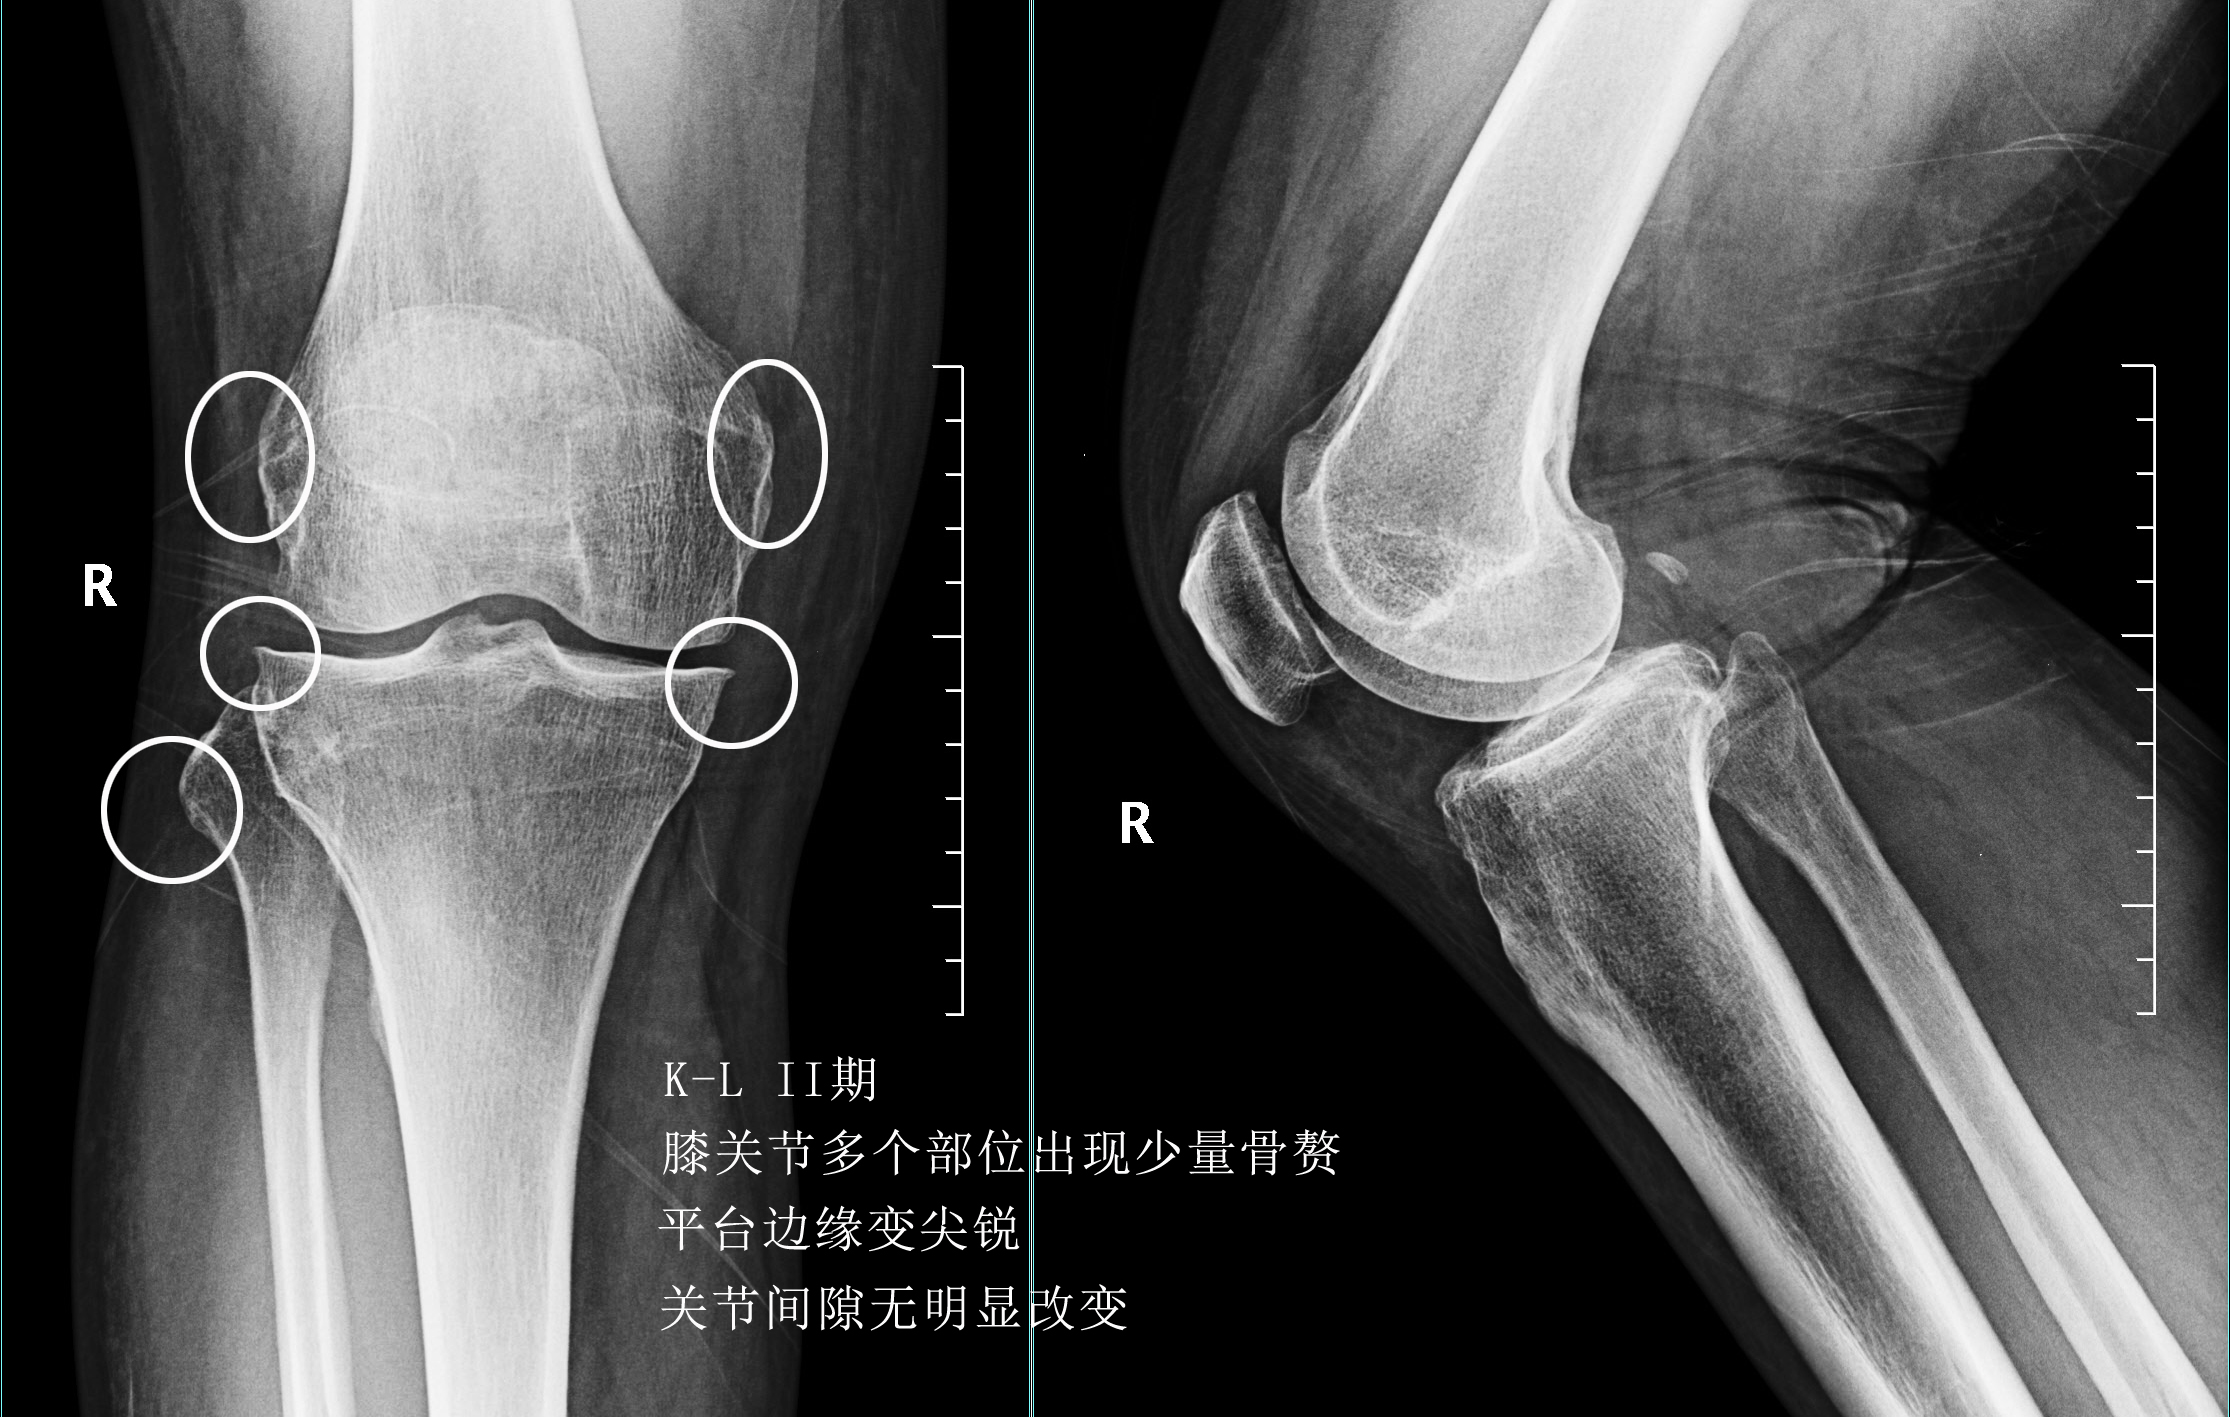

前面已经说到骨关节炎会导致骨赘的形成以及关节间隙的狭窄,所以我们依靠膝关节x片子来初步判断骨关节炎的病情,通常我们采用K_L分期判断病情。

二期患者:2期的患者关节的那个骨赘就已经开始明显增多了,但是这个时期关节的间隙仍然不会发生狭窄,这就说明关节内的软骨虽然已经有了磨损,但是磨损的程度还可以,不是特别的重。

三期患者:3期的患者不仅有了骨赘大量形成,而且关节间隙已经开始发生了明显的狭窄,患者的症状会越来越严重,很多会表现出来蹲起的疼痛,甚至有的患者不能长时间的行走,否则次日关节就会有明显的肿胀,有的患者在屈伸关节的过程当中会听到响声,类似于冬天我们用脚踩雪的那种响声。

在此阶段我们通常仍然会采取关节内注射的办法以及一些保守治疗的办法,缓解患者的痛苦。患者也可以口服仙灵骨葆这一类的中成药。

四期患者:4期的骨关节炎患者关节已经出现了严重的畸形,这个时期患者会非常的痛苦,关节会有严重的畸形,通常不能行走很长的距离,有一些患者甚至行走500米就疼痛难忍了。而且患者通常会出现比较明显的休息痛以及静息痛,什么意思呢?就是说,不动也痛。

此时我们只有通过进行关节置换手术的办法,才能帮助患者来解决痛苦。医生也知道很多患者不想做全膝关节置换术,所以说现在也研究出来单髁的置换手术,也算是一种保膝治疗。